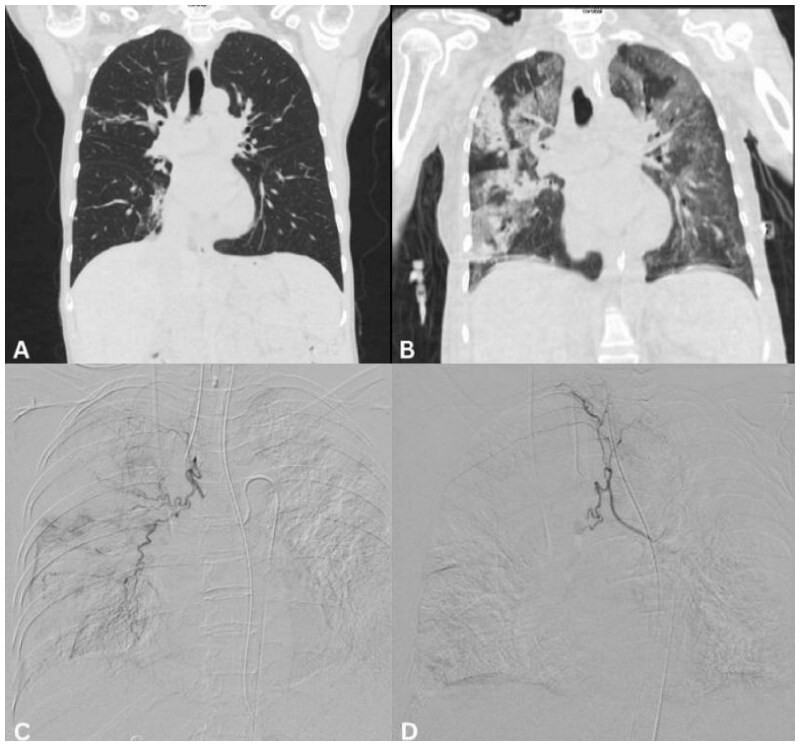

Haemoptysis in patients with lymphoma and leukaemia can present a therapeutic challenge, given that it is often associated with underlying impairments of haemostasis and immunosuppression. Bronchial artery embolization (BAE) is a mainstay in the treatment of haemoptysis, typically in those requiring emergent management. In this case series, the role of BAE in patients with lymphoma and leukaemia was evaluated. A total of 5 patients were identified between August 2010 and August 2022. Three patients were diagnosed with lymphoma (classical Hodgkin's lymphoma, diffuse large B-cell lymphoma and extra-nodal marginal zone lymphoma) and 2 patients were diagnosed with leukaemia (1 patient with acute myeloid leukaemia and the other with chronic lymphocytic leukaemia). All patients were thrombocytopenic [77.6 ± 28.5 × 109/L (mean ± SD)], at presentation. Three patients had concurrent lung infection at the time of their presentation. Technical success was achieved in 4/5 patients (80%). Clinical success was obtained in 4/5 patients (80%). Recurrence following embolization was seen in 2 patients. Three patients died within 30 days following embolization (from deteriorating respiratory function). Bronchial artery embolization for haemoptysis in patients with lymphoma and leukaemia is safe and feasible. Concurrent lung infection is potentially of significance with regard to initial presentation and overall outcomes following embolization. In select patients, BAE may provide a therapeutic option, though further investigation is required.